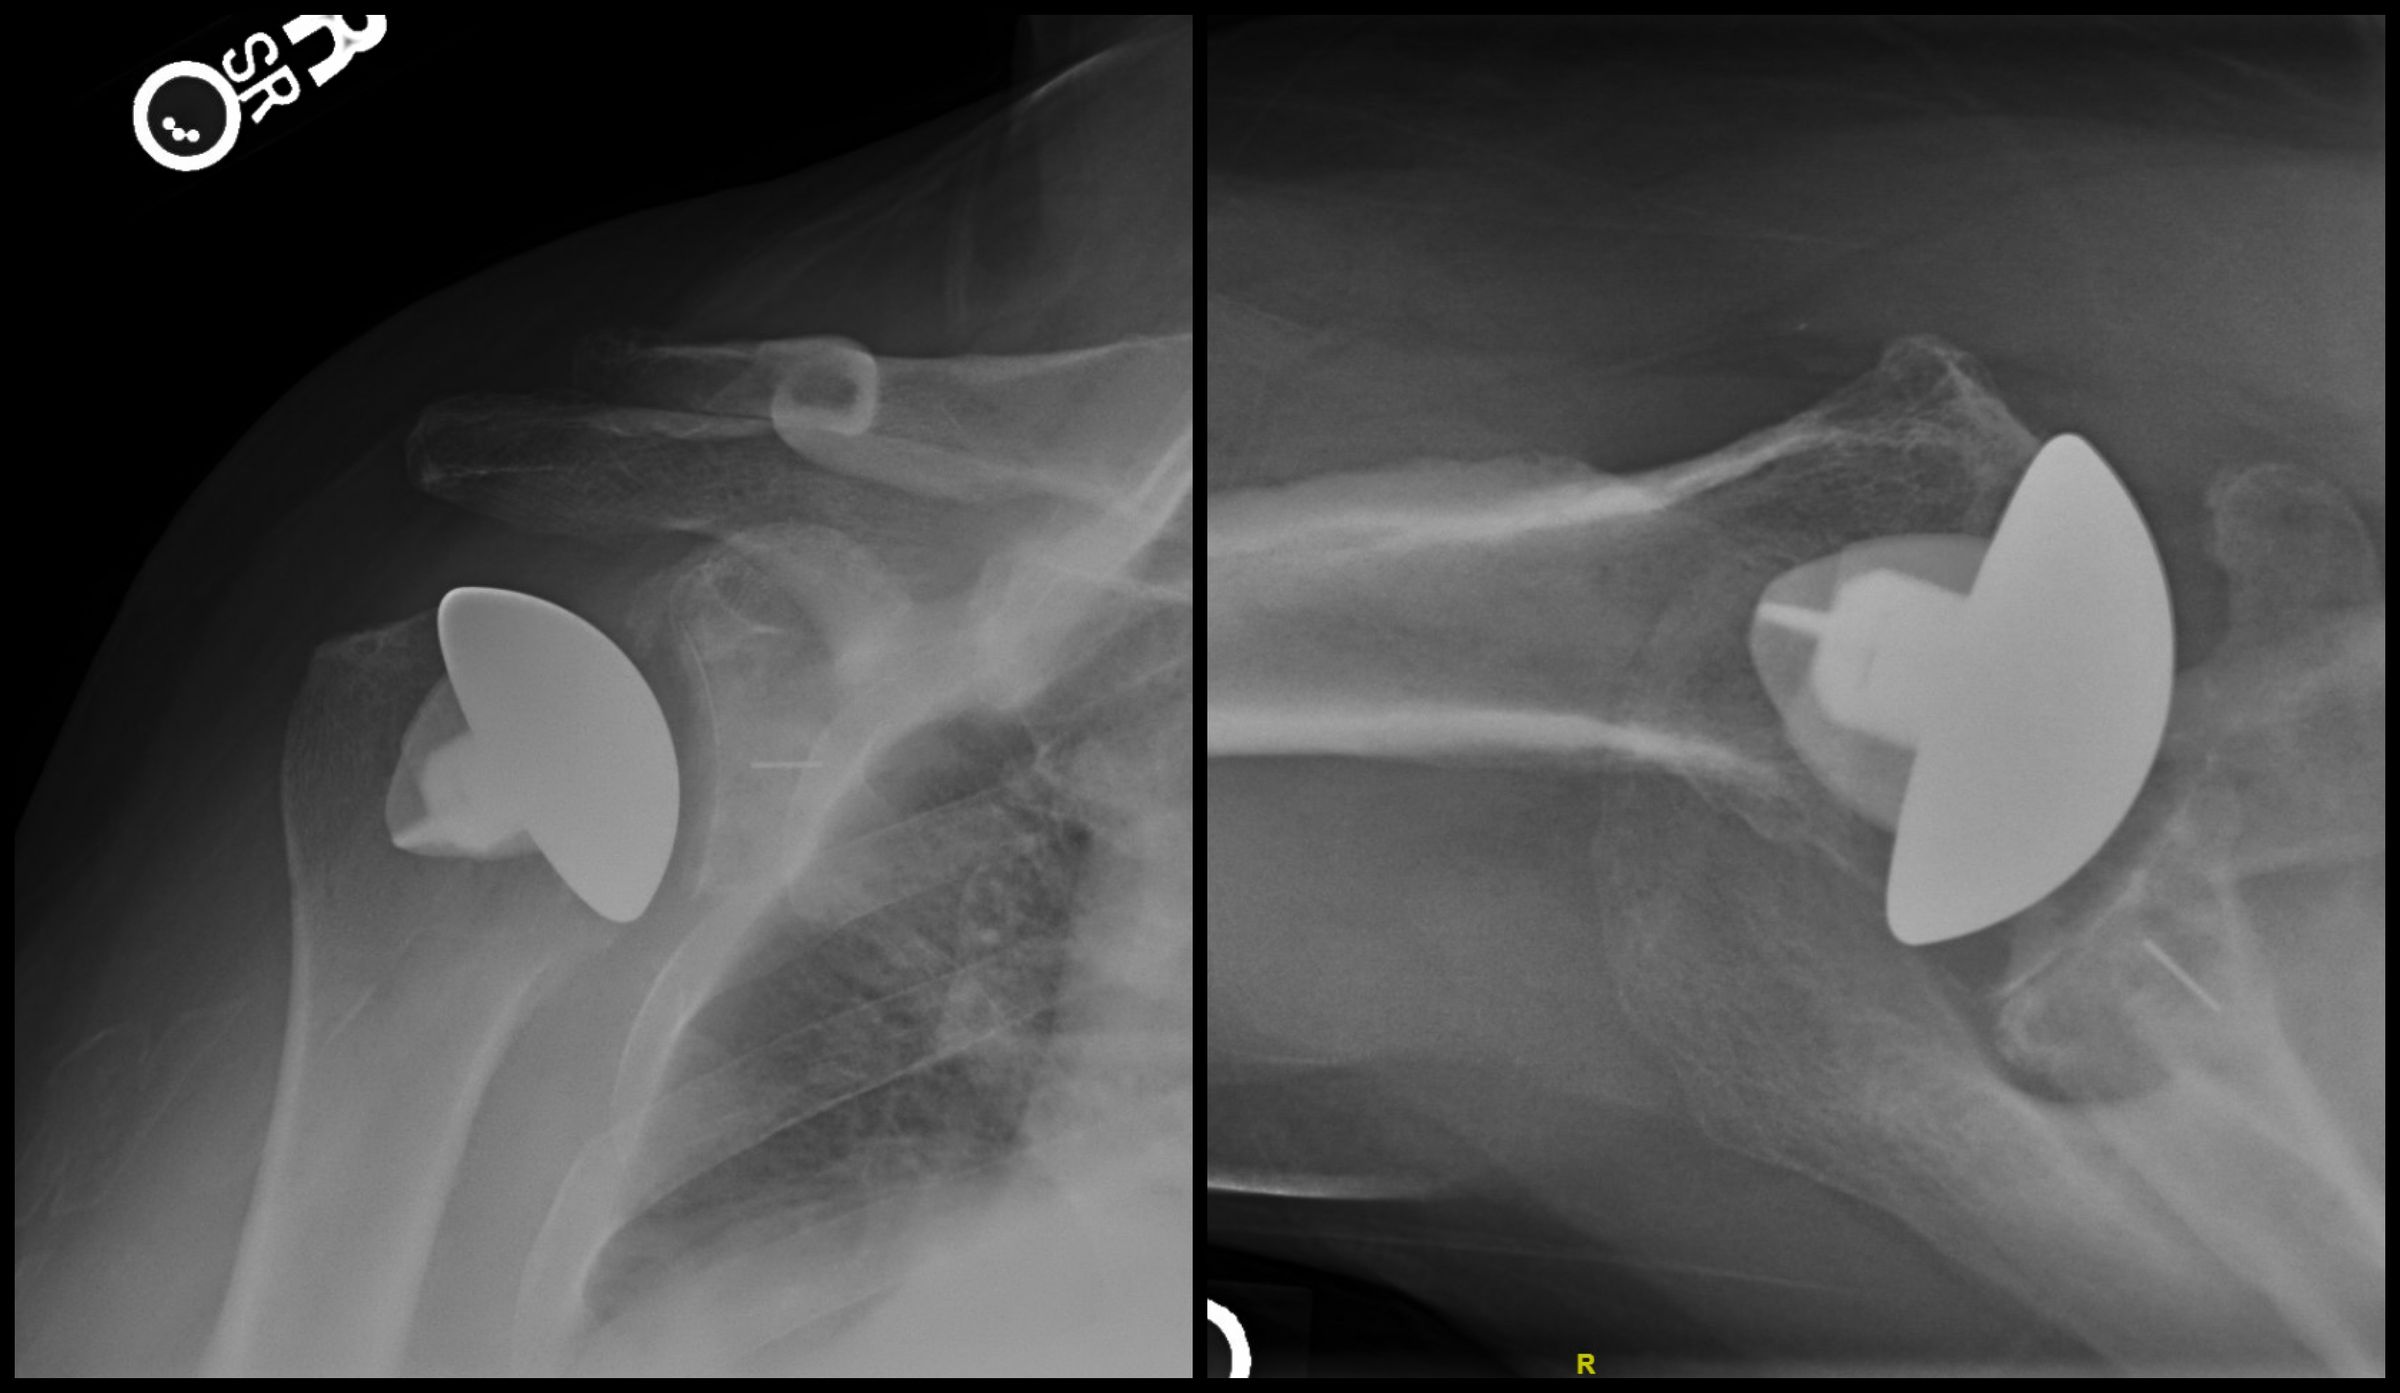

From www.caseclips.com

Anatomic Total Shoulder Arthroplasty Shoulder X Ray Technique    the shoulder series is fundamentally composed of two orthogonal views of the glenohumeral joint including. Provides better detail of cortical and trabecular bone structures than mri at cost of higher radiation exposure.  the shoulder ap view is a standard projection that makes up the two view shoulder series.  imaging evaluation of shoulder disorders should begin with radiographs.. Shoulder X Ray Technique.